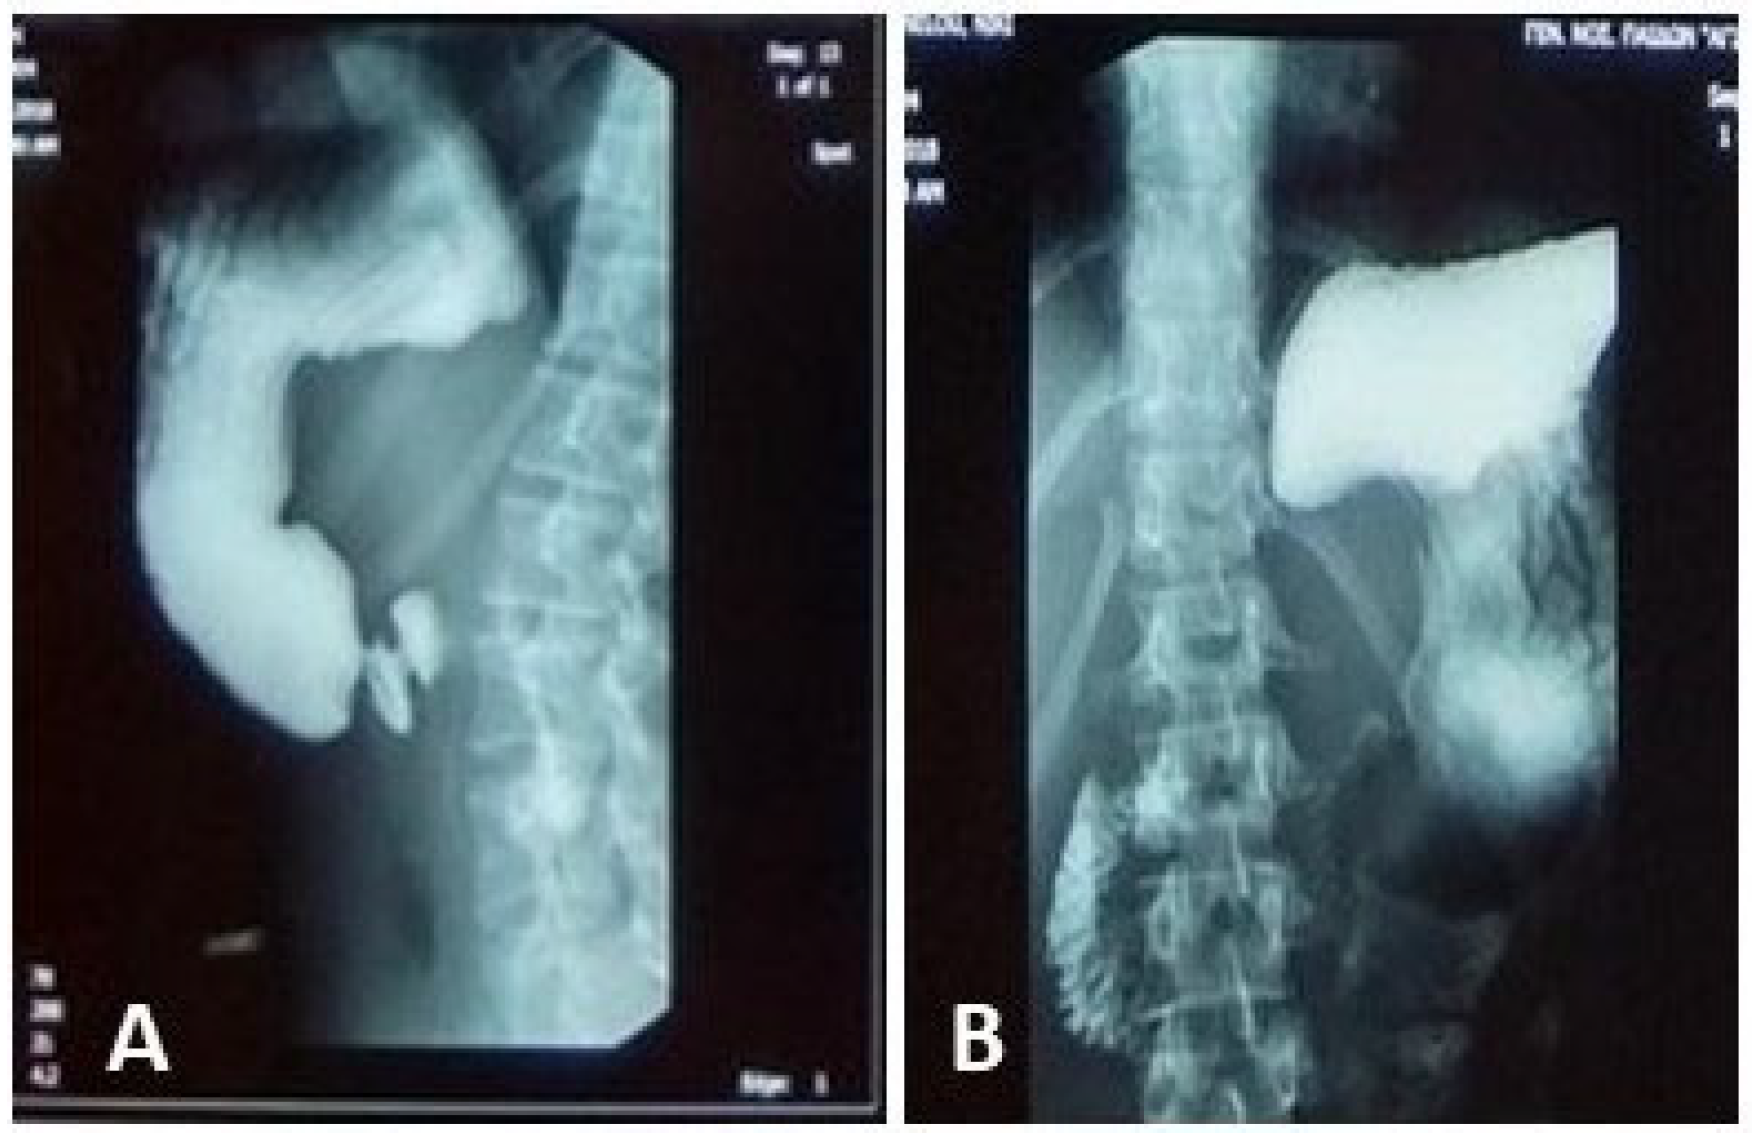

An upper GI contrast study demonstrated an incomplete fixed stenosis due to an apparent extrinsic pressure effect on the second portion of the duodenum, which impeded the passage of contrast medium. No intrinsic strictures or obstructive lesions were identified. Additional findings included antral dyskinesia and antiperistalsis, evidenced by delayed passage of contrast material into the duodenal bulb. A folding of the gastric fundus was also noted Figure 1.

Figure 1. Upper GI contrast study: incomplete fixed stenosis due to an apparent extrinsic pressure effect on the second portion of the duodenum. (A): Delayed progression of contrast material into the duodenum; (B): Gastric cascade configuration.